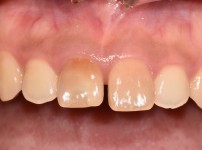

임플란트 재식립 사례

임플란트